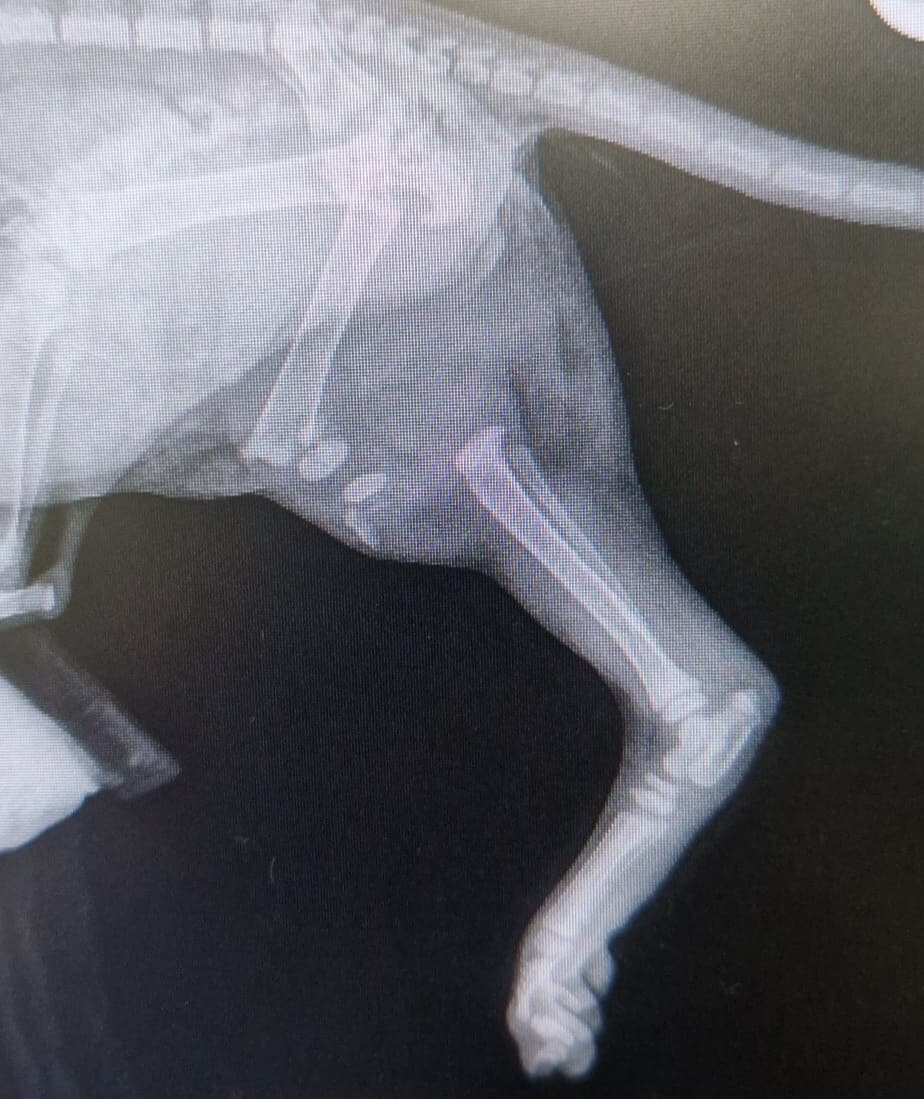

The charity confirmed the youngster’s leg was completely broken, and the vet had no choice but to amputate it.